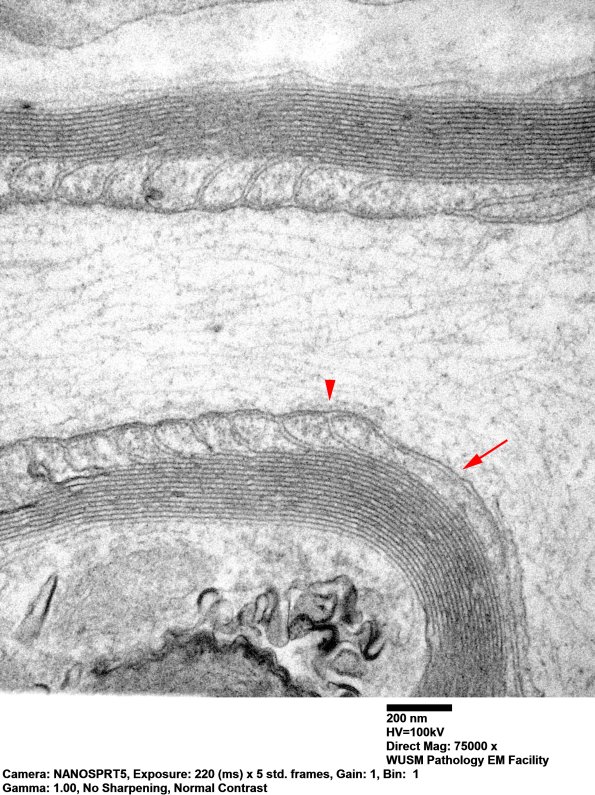

In these two images notice the difference between the internodal axolemma (arrow) and the paranodal effects on the axolemmal structure (arrowheads). (electron micrographs)